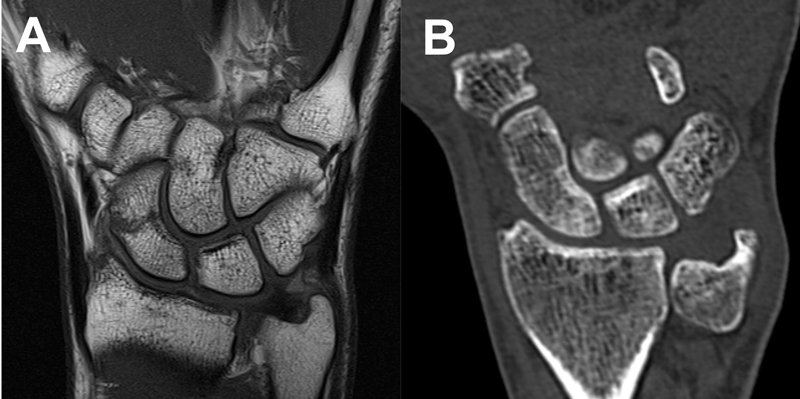

Skafoideumfrakturer läker utan kallusbildning [42], vilket medför att benläkningen är mycket svår att visualisera med konventionell röntgen. Detta gör att bedömningen av läkning i skafoideumfrakturer är osäker med denna metod [43]. DT med rekonstruktioner i skafoideums längsaxel ger möjlighet till en bedömning av den trabekulära benstrukturen i anslutning till frakturen och i vilken grad benläkningen överbryggar frakturspalten. Detta medför att DT är överlägsen konventionell röntgen för bedömning av frakturläkning [34, 44]. En MRT-undersökning visar enligt vår erfarenhet patologisk signal under lång tid efter att en skafoideumfraktur har läkt och ska därför inte användas för att bedöma grad av läkning.

Vid läkningsbedömning av skafoideumfrakturer med DT rekommenderas att visningsplanen i röntgenprogramvaran ställs in i skafoideums längsaxel, och därefter kan granskaren skrolla igenom frakturen i sagittal- och frontalplan. Om bentrabekler vuxit över frakturen längs med mer än 50 procent av frakturlinjen kan frakturen betraktas som mobiliseringsstabil [44] (Figur 7).

Figur 7. En odislokerad midjefraktur endast synlig på MRT (A). Efter 6 veckor uppvisar DT läkning med överväxt av bentrabekler (B).